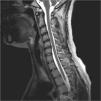

Focalidad neurológica en una paciente con lupus eritematoso sistémico

E. García Melchor, B. Mora Peris, G. Espinosa Garriga

Servicio de Enfermedades Autoinmunes. Hospital Clinic. Barcelona. España